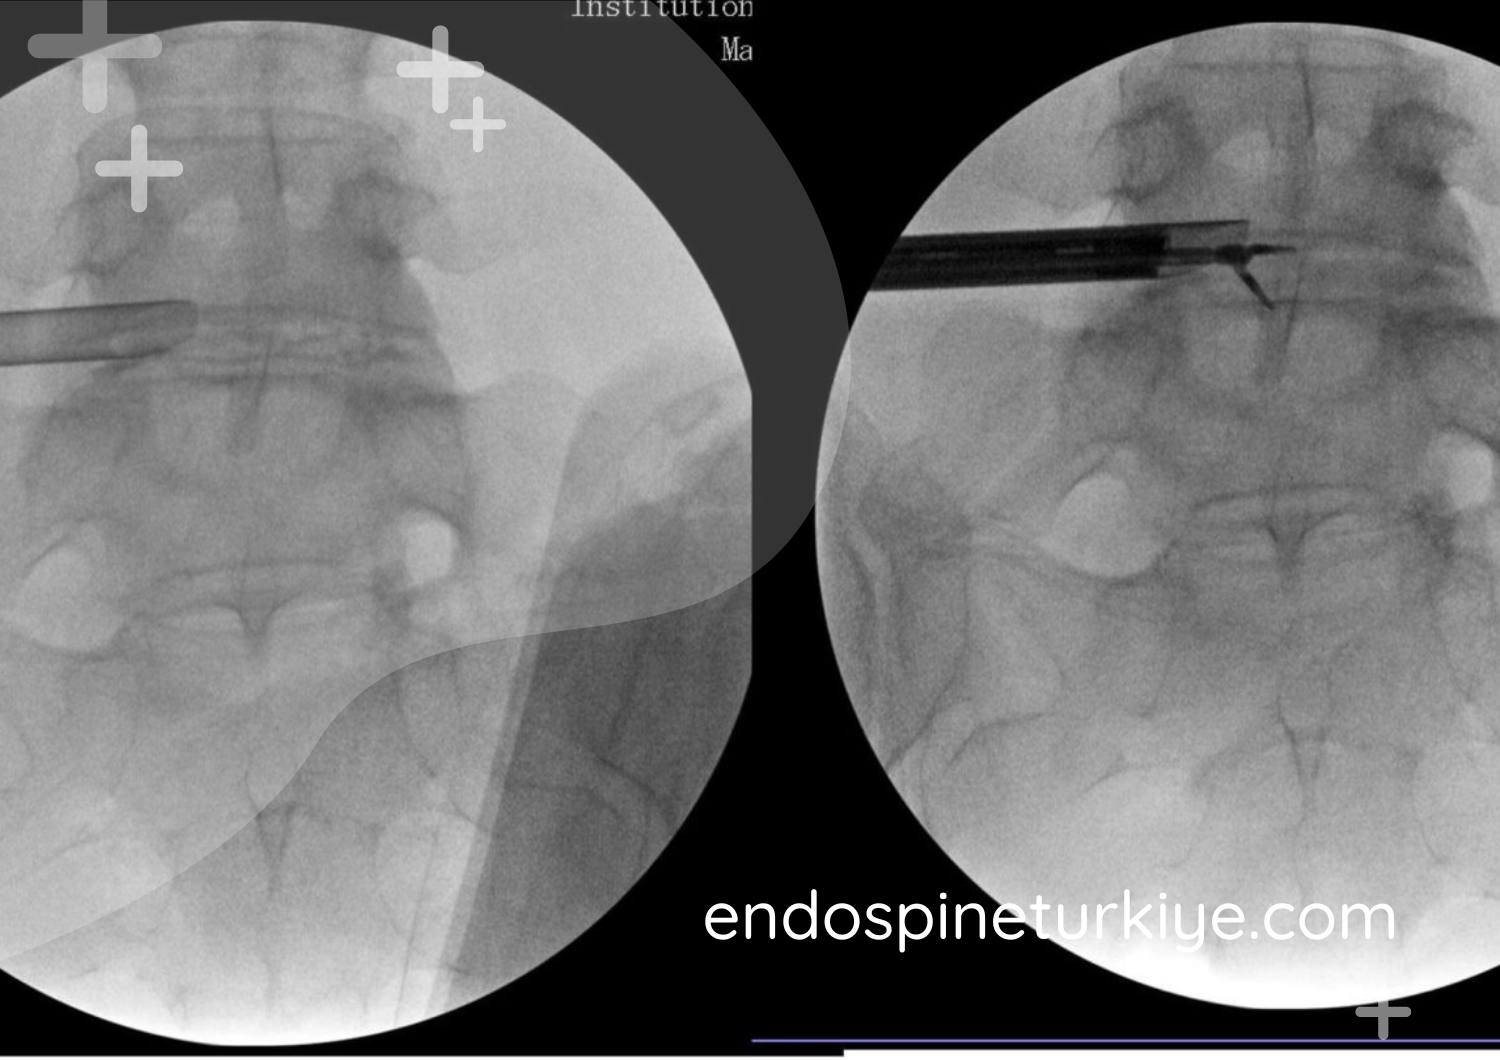

Op. Dr. Rifat Saygın Altınağ tarafından PELD (Perkütan Endoskopik Lomber Diskektomi) tekniğiyle gerçekleştirilen 6mm kesi ile cerrahi; ameliyat günü ayağa kalkma, ertesi gün eve dönüş. Tam kapalı endoskopik bel fıtığı cerrahisinde Türkiye'nin referans noktası.

6mm'lik açıklıktan endoskop konumlandırılır, HD görüntüleme altında fıtık materyali uzaklaştırılır.

Bel fıtığı tedavi öncesi MR görüntüsü - sinir basısı görülen lomber disk hernisi Tedavi Öncesi

Bel fıtığı tedavi sonrası MR görüntüsü - endoskopik ameliyat ile sinir basısı giderilmiş Tedavi Sonrası

MR görüntülerinde endoskopik bel fıtığı ameliyatı öncesi ve sonrası karşılaştırma